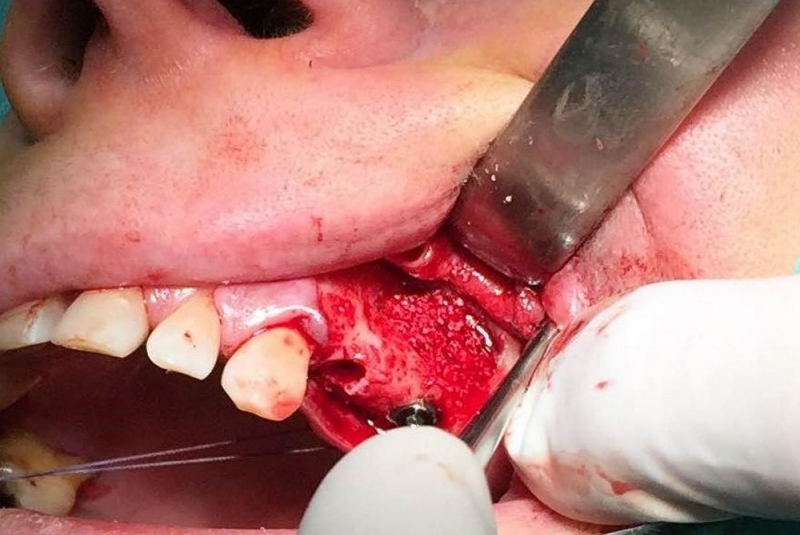

- Implantológia:

1. nadstavba kosti augmentačnými materiálmi (umelé kostné tkanivo, sinus lift a pod.)

2. implantológia, vrátane 3D - dentálneho CT